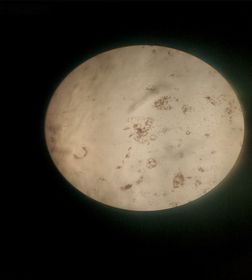

Observaciones

En la muestra sanguínea del Sapo se observa un tipo de célula que no poseen los seres humanos llamada Azurofilos Se observa que los glóbulos rojos no poseen núcleo en comparación con los glóbulos blancos que si poseen.

Los glóbulos rojos al madurar pierden el núcleo para obtener mas espacio para las funciones que cumple como el transporte del oxigeno.Los glóbulos Blancos mantienen su núcleo También se logra determinar a partir de la observación que la cantidad de glóbulos blancos en la sangre es menor a la de los rojos.